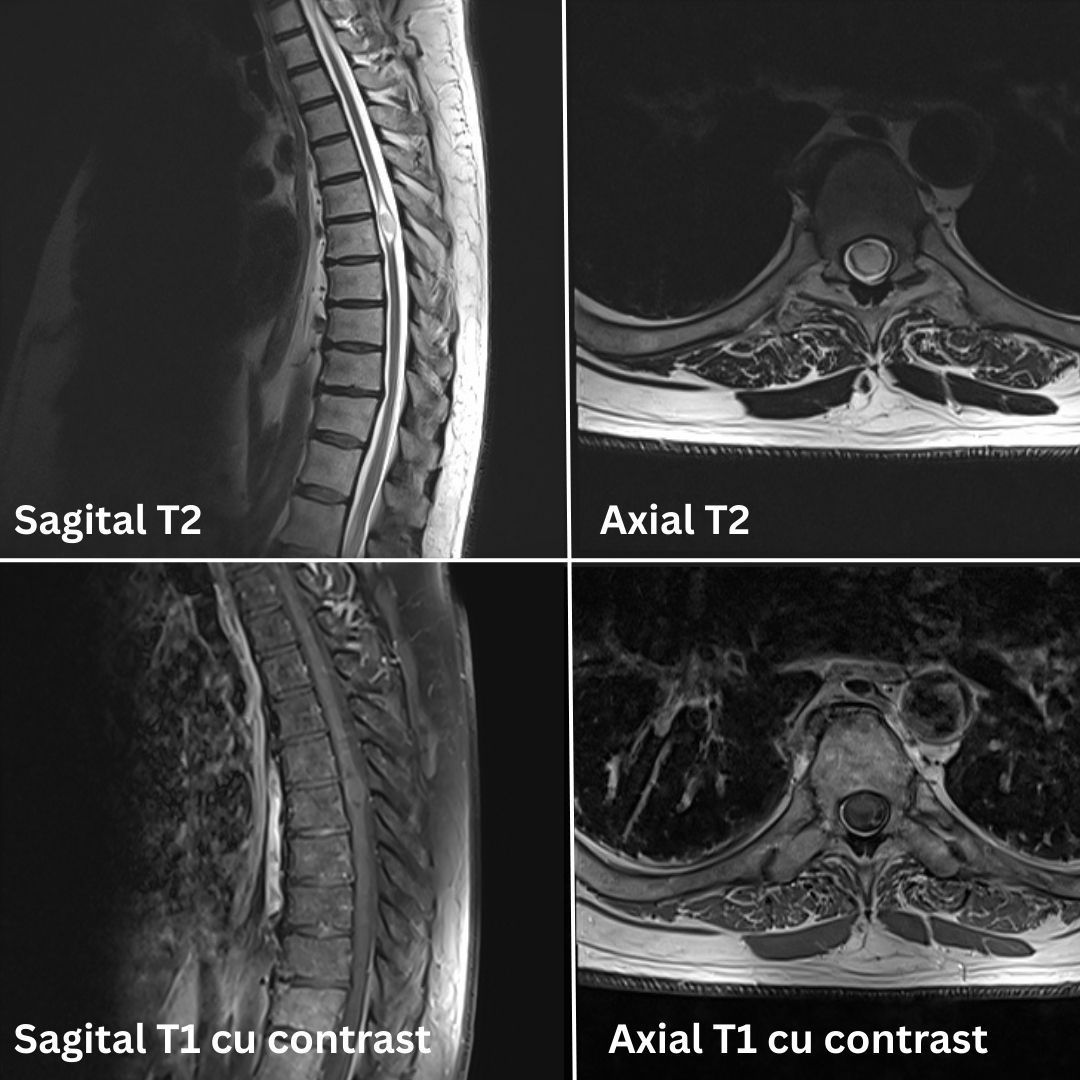

La SANADOR, investigația a fost realizată în siguranță sub anestezie generală, datorită echipamentelor de anestezie și monitorizare compatibile cu mediul RMN. Examinarea, realizată cu ajutorul unui echipament performant RMN 3 Tesla, a evidențiat o tumoră intramedulară localizată la nivel toracic (T6).

Examenul RMN 3 Tesla efectuat la Spitalul Clinic SANADOR a evidențiat o tumoră intramedulară localizată la nivel toracic (T6)